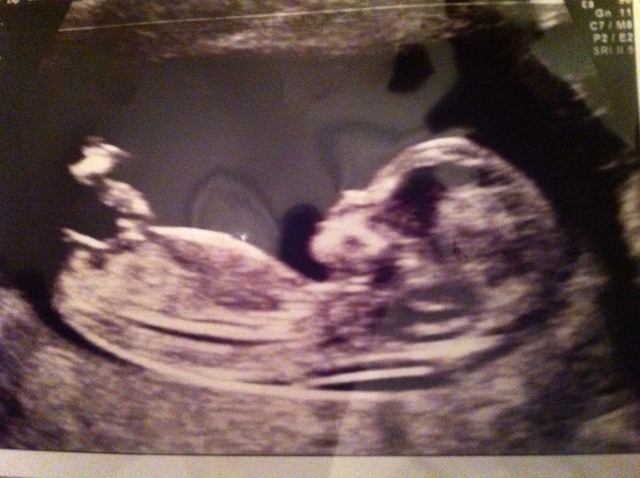

This is my 12+1 picture and I would love to hear your thoughts. My gender scan is not till 20 wks and I simply can't wait that long. Any comments are welcome :-)